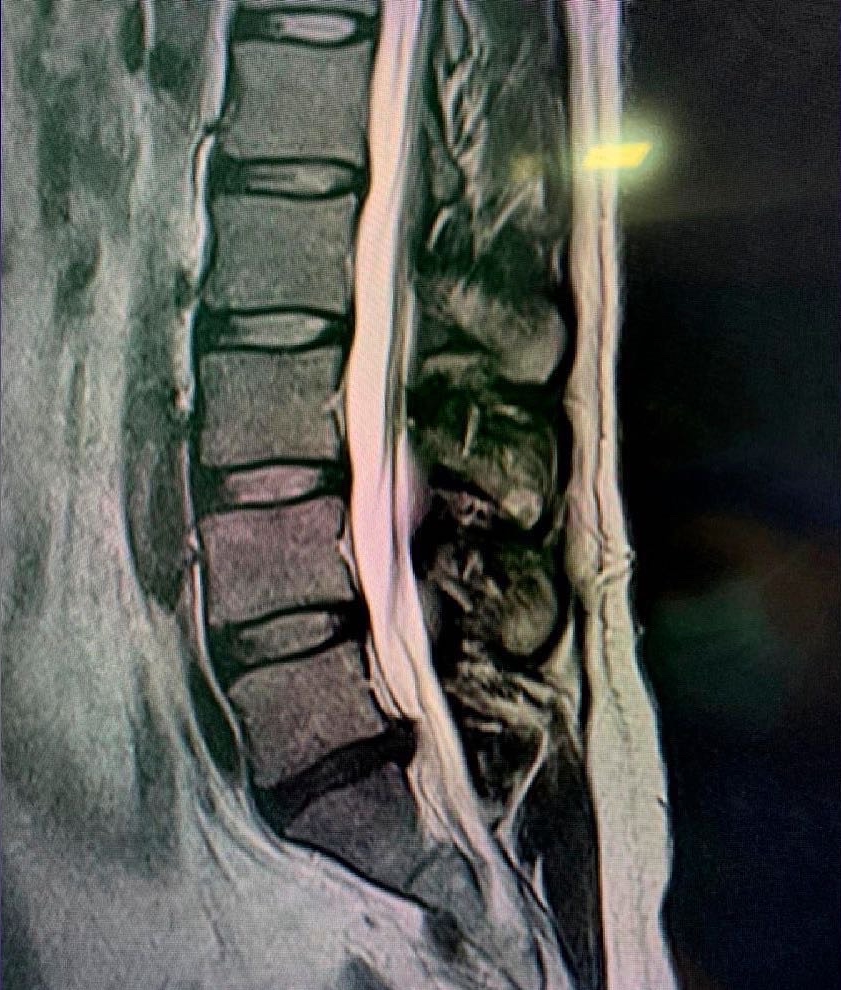

Disc disease is probably the disease most frequently treated by neurosurgeons and spine surgeons. Acute disc prolapse, bulging disc, herniated disc or ruptured disc are terms commonly used to describe failure of this structure. When symptoms are new, the typical sequence is first back pain in the region of the disc followed by nerve irritation pain in the arm or leg. This is called radicular pain, and some people use the term sciatica when the leg is affected.

A long-standing prolapsed disc may lead to chronic back, neck, arm, shoulder or leg pain, in any combination. All three parts of the mobile spine can be affected, but the lumbar and cervical regions are much more likely to cause symptoms. This is due to the relative mobility and loads placed on these regions.

Symptoms cause pain that usually worsens with loading and lifting and is relieved by rest or flexed positions. Arm or leg pain is very common and, when more severe, there may be limb numbness or weakness or hand dysfunction. The distribution of pain or neurological symptoms is determined by the affected nerve and depends on whether the disc is of cervical, thoracic or lumbar origin. When spinal cord compression is present, gait, balance and continence may be affected. Surgery is recommended when there is a significant neurological problem or if the pain does not respond well to simple measures. Simple discectomy, microdiscectomy, minimally invasive discectomy or anterior cervical discectomy and arthrodesis can be very effective in selected patients who do not respond to rest, analgesia and other conservative measures.

Another problem that commonly affects the disc is degenerative disc disease which can cause disabling symptoms such as pain, loss of limb strength, difficulty walking, etc. This can affect any region or area of the spine, but mainly the cervical and lumbar spine. These problems may require treatments ranging from physical therapy to complex surgeries involving disc replacement and support with screws.

Instability and deformity

Abnormal alignment or angulation of the spine can cause disabling symptoms. The most common form of this is the result of wear and tear changes affecting the intervertebral discs and overlying facet joints. This can result in the movement or displacement of one vertebra relative to its neighbor, a phenomenon known as spondylolisthesis. A congenital form of this is also seen in the lumbar spine and results from a defect in the bridging bone called the pars. When symptomatic or progressive, a decompression or fusion procedure can be very effective. Generally, an instrumented fusion would be recommended in these cases.